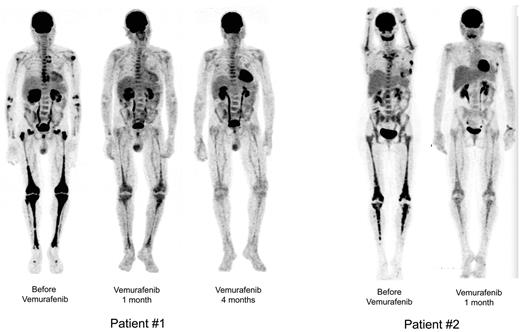

Sequential PET. Patient no. 1 (left): Sequential PET showing high initial pathologic uptake of 18F-fluorodeoxyglucose in soft tissue and bones before vemurafenib treatment, and significantly less uptake after 1 month and major regression after 4 months of vemurafenib treatment. Patient no. 2 (right): Similar substantial reduction of 18F-fluorodeoxyglucose uptake in all tissues involved. Reconstruction algorithm: OSEM_3D (5 iterations, 16 subsets, 9 mm Gauss filter). Volume rendering: Maximum Intensity Projection (Osirix Software). Display: BW inverse logarithmic table and range (min value = 0, max = 2.7 for SUV).

Vemurafenib was started at 1920 mg/d (b.i.d.) on April 19, 2012 and was tapered to 960 mg/d from day 30 due to erythema, and was thereafter maintained at this dose. Within a few days of the initiation of treatment, itching disappeared. Evaluation on day 30 showed an improvement of creatinine (190 to 161μM), GGT (936 to 300 U/l) and alkaline phosphatase (644 to 177 U/l) values. On day 62, GGT was 183 U/l, PAL 146 U/l, and creatinine 170μM. CRP was normalized by day 30 (Figure 4), and remained under 5 mg/L on day 62. PET was performed after 30 days of vemurafenib treatment and the findings compared with those obtained 4 months earlier: there was a substantial improvement of all lesions (Figure 1), with a mean Standardized Uptake Value (SUV) change of −70% (range, −66% to −80%); the change within soft tissue and bone was similarly −70% (range, −51% to −78%; supplemental data, available on the Blood Web site; see the Supplemental Materials link at the top of the online article). Thoraco-abdominal CT after 37 days of treatment showed a significant reduction of periaortic infiltration (Figure 3). This cannot be attributed to PEG-IFN treatment, withdrawn on March 31, 2012, because several other markers clearly indicated that the patient was a nonresponder (high CRP values, hydronephrosis and pyelocalicial dilation, worsening of PET findings). Hydronephrosis and pyelocaliceal dilation resolved completely. Note that the PET assessment at 4 months showed that the decrease of FDG uptake had been sustained: uptake was lower than that observed after the first month (Figure 1). Aortic MRI after 4 months disclosed a marked regression of peri-aortic sheathing relative to that observed by CT-scan in May 2012. The CRP value remained low on day 123 of treatment (Figure 4).

After a few days, histiocytic skin lesions resolved (Figure 2), and the pain in the right eye disappeared such that morphine could be stopped. A new skin biopsy confirmed the absence of histiocytic infiltration of the epidermis and hypodermis. CRP was normalized by day 30 (Figure 4), and was 5.2 mg/L (N < 5) on day 48. PET 31 days after initiation of vemurafenib was compared with that performed 2 months earlier: the change in the mean SUV was −57% (range, −51% to −67%) and that in soft tissue and bone was −70% (range, −56% to −78%; Figure 1 and supplemental data). Orbit MRI on day 36 showed a 26% to 66% decrease of the retro-orbital infiltration (Figure 3 and supplemental data). Thoraco-abdominal CT on day 39 demonstrated a 30% to 40% decrease of the posterior and lateral peri-aortic infiltration (Figure 3), and the absence of the previously observed interlobular septa thickening, characteristic of pulmonary involvement of ECD. The CRP value remained below 5 mg/L on day 141 of treatment (Figure 4), and the patient was asymptomatic, with the absence of orbital pain.

PET assessment of treatment of cases of ECD has not previously documented such rapid efficacy. IFN treatment has a much more subtle and slow effect on the regression of uptakes.13 For patient no. 1, there was a mean regression of 70% of visceral and bone 18F-fluorodeoxyglucose uptakes at month 1, and the therapeutic response observed at month 4 was even better. Substantial regression of peri-vascular sheathing and disappearance of hydronephrosis (CT), as well as normalization of measures of CRP and liver enzymes confirmed the excellent therapeutic efficacy. The benefits of treatment were similar in patient no. 2, with 57% to 70% regression of visceral and bone 18F-fluorodeoxyglucose uptakes, regression of peri-aortic and orbital infiltrations, and normalization of CRP values.